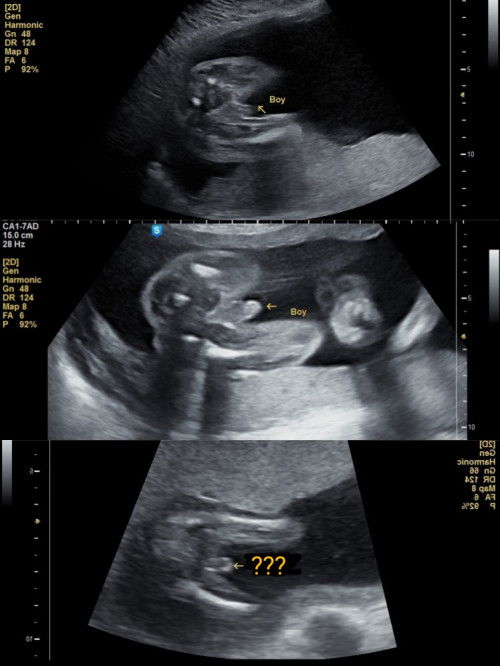

Boy or girl??

sy dah ada 2 anak lelaki,skarang mengandung anak ketiga..morning sickness teruk dari awal mengandung smpai skarang dah 16 weeks pon masih ada morning sickness,anak pertama dan kedua xde pon mcm ni...ni nampak mcm girl atau boy?ni scan anak pertama,kedua dan ketiga..#bantujawab #ingintahu